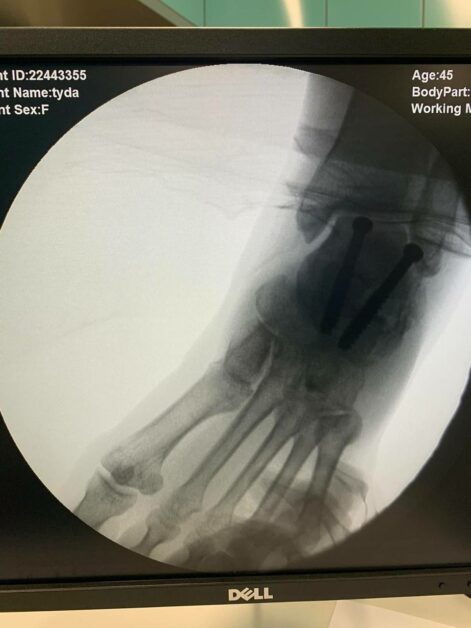

លោកស្រី សឿន សំណាង ពលការិនីខ្មែរ ដែលទៅប្រកបរបរនៅប្រទេសថៃ បានជួបគ្រោះថ្នាក់បាក់កែងជើង ដោយសារព្យុះរញ្ជួយដី កាលពីថ្ងៃទី ២៨ ខែមីនា ឆ្នាំ ២០២៥រូវបានទទួលការព្យាបាលភ្លាមៗនៅ មន្ទីរពេទ្យមិត្តភាពកម្ពុជា-ចិន ព្រះកុសុមៈ។

ក្រោយពេលបញ្ជូនមកមន្ទីរពេទ្យ លោកស្រី សឿន សំណាង បានទទួលការវះកាត់ដោយប្រកបដោយសុវត្ថិភាព តាមការយកចិត្តទុកដាក់ជាទីល្អពី សម្តេចមហាបវរធិបតី ហ៊ុន ម៉ាណែត និងលោកជំទាវបណ្ឌិត ពេជ ចន្ទមុន្នី តាមរយៈសមាគម គ្រូពេទ្យស្ម័គ្រចិត្តយុវជនសម្តេចតេជោ (TYDA)។ កិច្ចការចំណាយទាំងអស់ ចាប់ពីការព្យាបាល ស្នាក់នៅ អាហារ និងការធ្វើដំណើរ ត្រូវបានឧបត្ថម្ភទាំងស្រុងដោយ សម្តេចធិបតី ហ៊ុន ម៉ាណែត និងលោកជំទាវ។